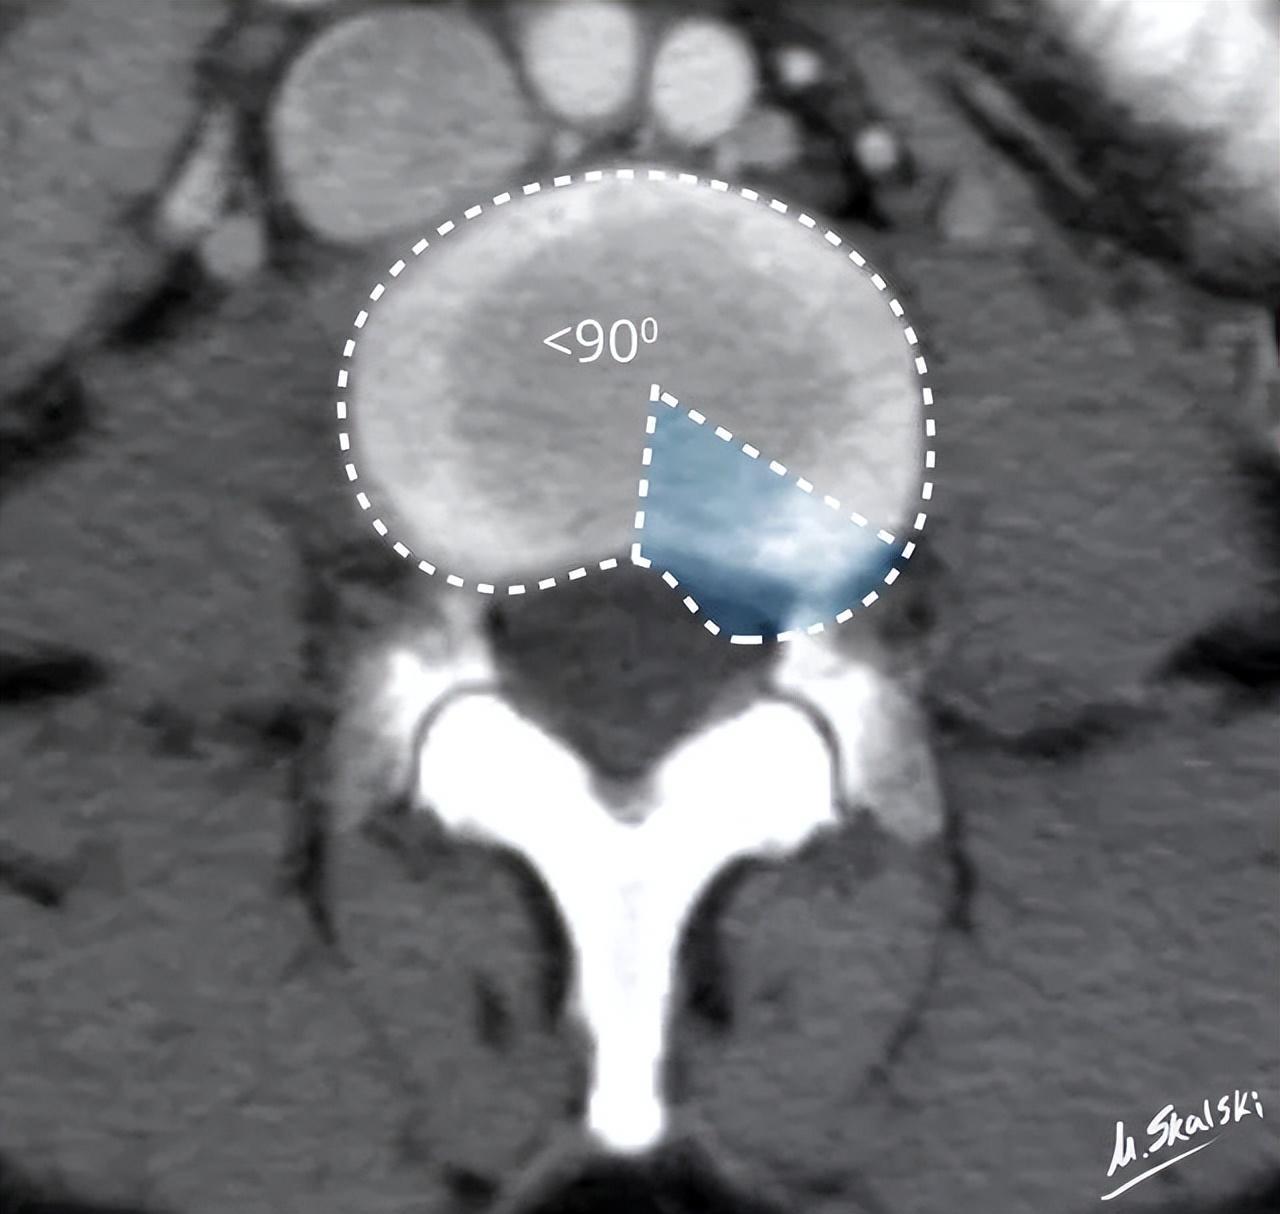

椎间盘膨出的影像学定义为:突出部分>椎间盘边缘的25%,或者突出的两边与髓核的中心的夹角>90°

突出部分小于椎间盘边缘的25%,并且基底部>突出部分的直径;突出椎间盘的两边与髓核的中心的夹角<90°